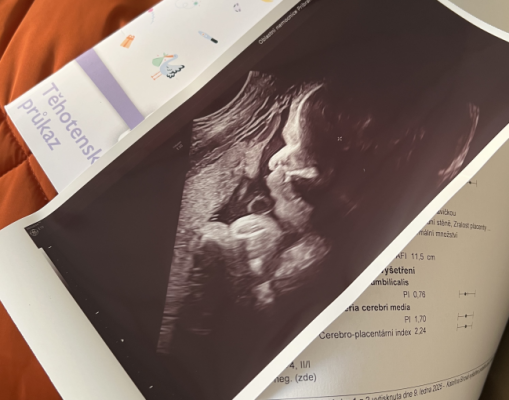

Přinášíme vám oblíbený seriál, ve kterém budeme sledovat náročné těhotenství maminky Katky doslova v přímém přenosu. Maminka Katka se s vámi podělí o své pocity, nálady, události aktuálních týdnů těhotenství. Nebudou chybět ani těhotenská vyšetření. Včetně jedinečného pohledu Katky na jejich rodinu, rodičovství jako partnerství a speciálně popíše i pohled chlapa na rodičovství. Tentokrát se máte opět na co těšit!